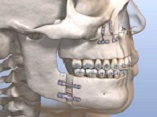

This special issue delves into the intricate world of head and neck disorders, encompassing the oral cavity, salivary glands, thyroid, pharynx, larynx, and craniofacial structures. Bridging the gap between foundational science and clinical innovation, this collection explores the full spectrum of diseases—from benign conditions like dental caries, periodontal disease, and temporomandibular joint disorders to malignancies such as oral squamous cell carcinoma, HPV-driven oropharyngeal cancers, and salivary gland tumors. By integrating dental, oral, and craniofacial health into the broader head and neck framework, this issue highlights the interconnectedness of these systems and their collective impact on patient well-being.